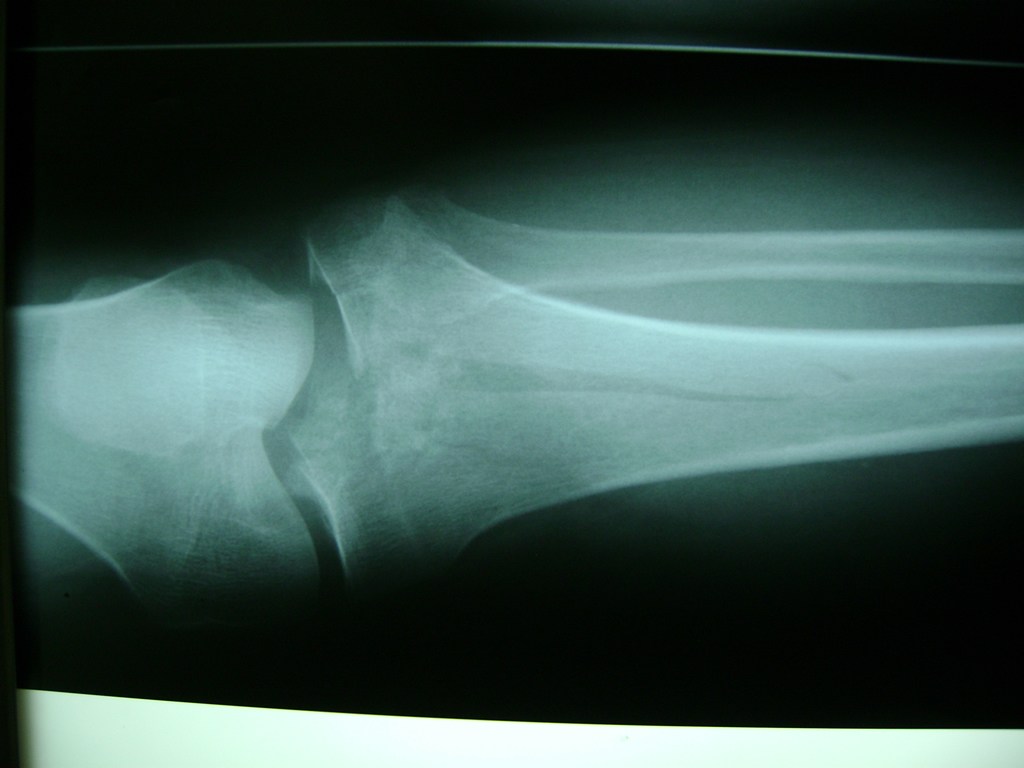

Cirugía de Fémur - Rodilla